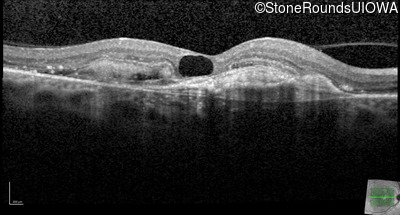

AR Stargardt Disease (IIA)

Age at visit: 59 years (Visit 3)

This 59 year old woman first noticed vision loss in her right eye a few months earlier. She has a cousin with Rhodopsin-associated RP.

Diagnosis & molecular findings

Disease Gene Allele 1 variant(s) Allele 2 variant(s) Inheritance mode

AR Stargardt Disease ABCA4 Arg219Thr AGA>ACA Gly863Ala (G)GA>(G)CA AR